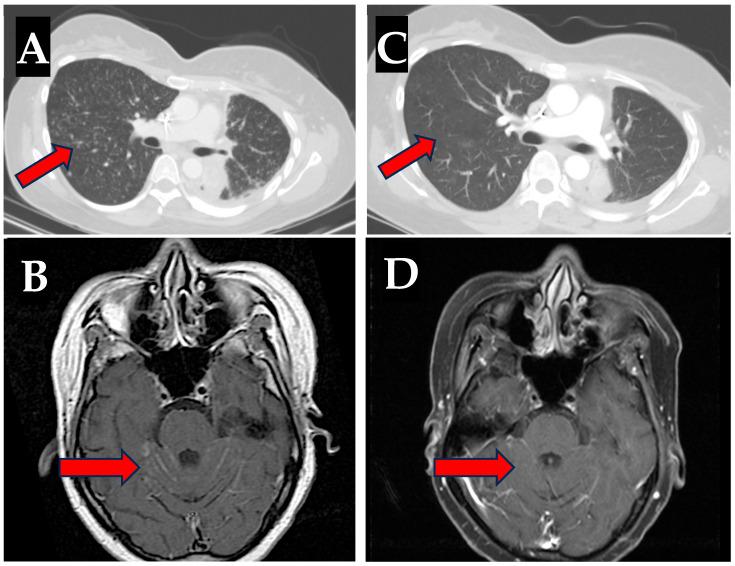

Background and Clinical Significance: Non-small-cell lung cancer (NSCLC) with EGFR mutations, particularly de novo compound mutations such as exon 19 deletions (Ex19del) with T790M substitutions, present a significant clinical challenge due to resistance to many treatments. While treating these patients, the administration of osimertinib, a third-generation EGFR inhibitor, after immunotherapy can lead to unique immune-related adverse events (irAEs), such as pneumonitis and, rarely, hepatitis. Case Presentation: A 36-year-old Filipino woman presented with metastatic NSCLC harboring de novo Ex19del and T790M mutations. Despite initial therapy with carboplatin and paclitaxel, followed by chemoimmunotherapy, the patient's disease progressed. She subsequently developed severe hepatitis from osimertinib after her prior immunotherapy with pembrolizumab. After the hepatitis resolved with high-dose steroids, osimertinib was switched to afatinib, but her disease rapidly progressed with new metastases. A second attempt at osimertinib rechallenge, with concomitant prednisone, resulted in substantial disease control, including improved leptomeningeal disease (LMD) and no recurrence of hepatitis. Conclusions: This case underscores the feasibility of rechallenging with osimertinib in patients who experience adverse events such as hepatotoxicity, provided that appropriate management strategies, such as steroid therapy, are employed. The successful rechallenge in this case highlights the potential of osimertinib as a viable option in advanced EGFR-mutant NSCLC, even after prior treatment-related complications.